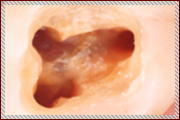

写真で見る、顕微鏡を用いた根の治療

お口の中は通常この様に暗く、目視だとなかなか細部までは見えません。 |

当院では顕微鏡を用いて上記のサイズに拡大して、細かい歯の根っこの治療を行いますので、神経を傷つけずに、リスクの少ない治療を心がけております。 |